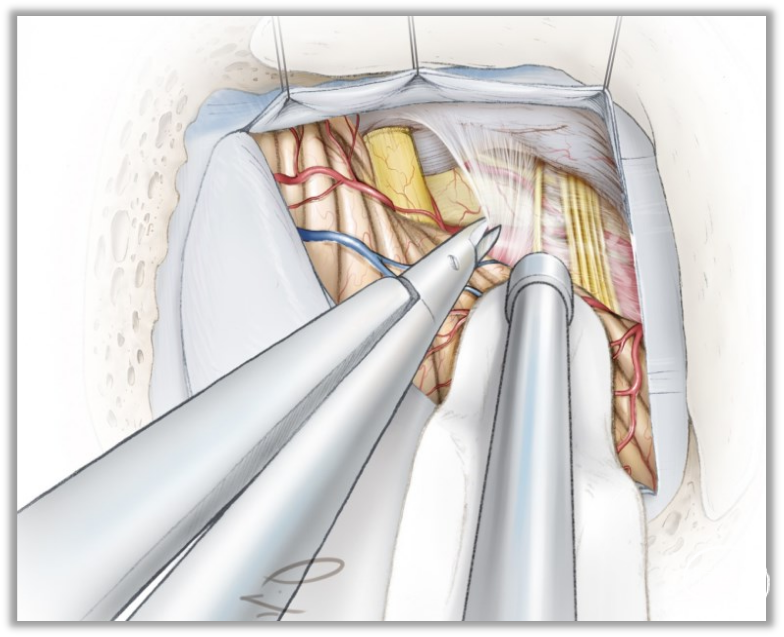

▼15.小脑绒球下入路

小脑绒球下入路(infrafloccular approach)最早由日本专家Matsushima提出。因为绒球和从Luschka孔突出的脉络丛从外侧遮挡面神经REZ区(下图),而且,在绒球和前庭蜗神经之间经常有黏连,还可能存在大量坚韧的蛛网膜小梁,因此从小脑外侧间隙很难暴露REZ区,还可能造成听力损伤。

此时重要的是要牢记面神经出脑干处位于舌咽神经入脑干处上方2~3mm。

绒球下入路(上图)就是抬起小脑的下外侧缘,打开舌咽神经和迷走神经后方的蛛网膜,便可暴露由Luschka孔突出的位于舌咽神经和迷走神经后面的脉络丛,将脉络丛从舌咽神经后缘轻轻分开,以暴露舌咽神经与脑干连接处。脑板进一步向上将脉络丛从舌咽神经后缘上抬起,暴露范围向舌咽神经上方扩展数毫米,此处即为面神经与脑干的连接处(REZ区),恰位于前庭蜗神经的前下方。

▼17.锐性地分离后组颅神经的蛛网膜,并辨认出舌咽神经。

充分松解后组颅神经背侧蛛网膜,若松解不充分,就无法获得从下向上的视野。

充分松解的标准就是能看清后组颅神经出入延髓橄榄后沟的神经根丝。

充分释放脑脊液后,此后的操作可不用脑压板,采用吸引器来动态地牵开小脑,动态牵拉既会减少听力受损的概率,也会充分暴露术中所需要的解剖区域。